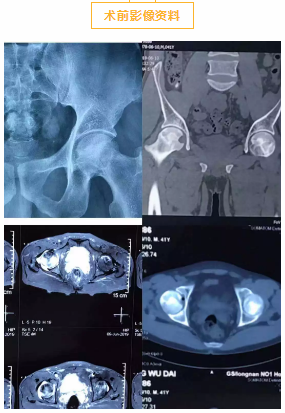

近日,我院骨一科成功开展一例股骨头坏死关节镜下病灶清除+同种异体骨植骨术。

患者,男,40岁,双侧髋部疼痛2年。查体:跛行,双髋关节处未见肿胀,未见明显皮肤发红,皮温不高,腹股沟处压痛(—),叩击痛(—),双侧髋关节活动轻度受限,不能完全下蹲及弯腰;双下肢等长,皮肤感觉及末梢血运良好。入院后诊断为:右侧股骨头坏死Ⅳ期,左侧股骨头坏死Ⅱ期。右侧关节面塌陷关节间隙变窄骨赘形成,已在我院行DAMIS右侧全髋关节置换术。经多角度评估、科室与青岛市市立医院帮扶专家孟烨教授会诊后,决定行关节镜下左侧股骨头坏死病灶清除+同种异体骨植骨术。手术顺利,术后患者恢复良好,无明显并发症发生。

该技术创伤小,关节镜下直接清除病灶,同种异体骨植骨增加了股骨头负重区软骨下骨的机械支撑,成骨作用强。该手术是早期股骨头坏死患者保髋的选择,有利于股骨头的修复与重建,同时不破坏股骨头本身的血液供应,创伤小,操作简单,值得临床推广使用。